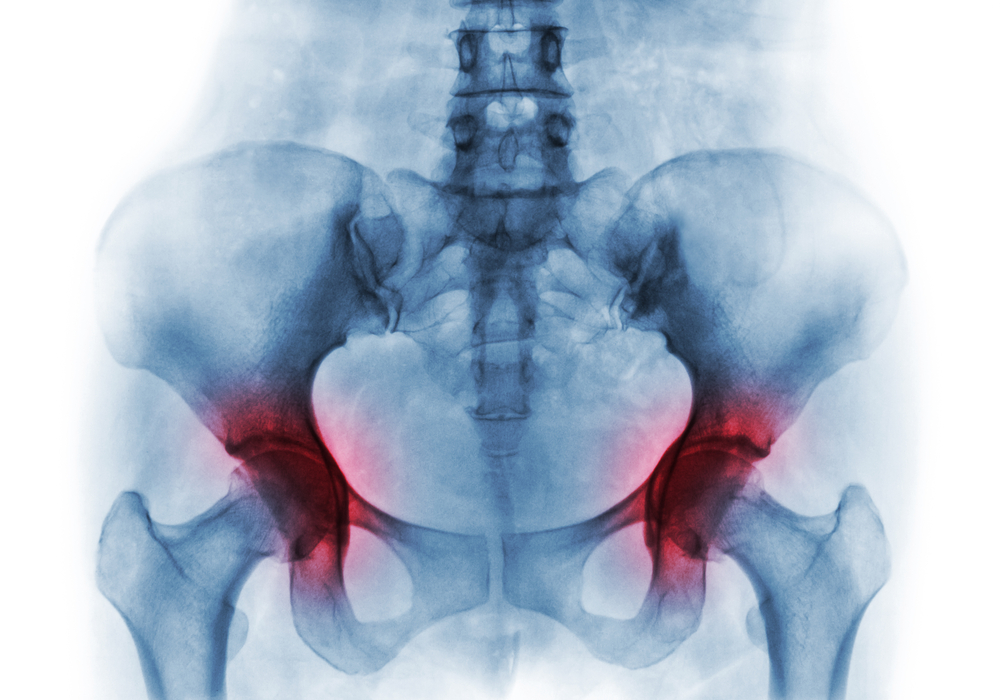

Kaip radiacija veikia kaulus?

Spindulinė terapija sutrikdo kraujo tiekimą kaulams, todėl jie tampa neatsparūs infekcijoms, sunkiai gyja po traumų ar chirurginių intervencijų (pvz., dantų rovimo). Dėl pažeistos kraujotakos kaulas ir šalia esantys audiniai praranda galimybę pilnai atsinaujinti ir pradeda žūti. Ypač didelė rizika kyla žandikauliui, nes gydant galvos ir kaklo vėžį radiacija paveikia šią zoną tiesiogiai, o burnos bakterijos dar labiau padidina pavojų susirgti osteoradionekroze.

Dažniausia priežastis – radioterapija galvos ir kaklo srityje. Didžiausia rizika kyla tiems, kurie gydymo metu gavo didesnę kaip 60 grėjų radiacijos dozę.